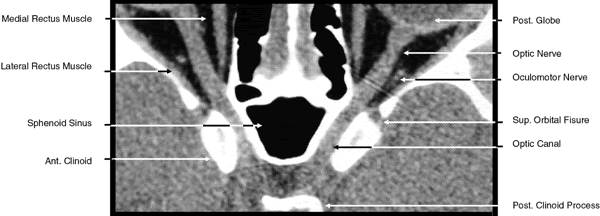

2D CT imaging is most frequently performed in the axial plane (Fig. 2). The bony anatomy of the orbit, optic canal, and intracranial cavity determines the exact orientation of this plane to provide the best visualization of both bone and soft tissue. The bony orbit is shaped like a quadrilateral pyramid lying on its side and with its base facing anteriorly. The medial orbital walls are almost parallel, although they tend to converge toward the midline in their posterior aspect. The lateral orbital walls diverge at approximately 45 degrees to the midline. The orbital axis is about 23 degrees divergent from the midline. The orbitomeatal line (Reid's baseline or the Frankfurt-Virchow line) is an important radiologic landmark for imaging the orbital structures. It is a line that extends from the upper margin of the external auditory meatus to the inferior orbital rim. The orbital floor is at approximately a -20-degree angle with this line, and the optic canal is at approximately a -30-degree angle with this line. Axial scans of the orbit are performed parallel to the orbitomeatal line, in contrast to axial scans of the intracranial contents, which are performed in a plane parallel to the orbital roof, which is at a + 30-degree angle to this line. The optic chiasm is also best imaged in a plane parallel to the orbitomeatal line. Although both the optic canal and nerve can be adequately visualized with axial scans parallel to this plane, scans of these structures are more precisely performed if the image plane is at a -30-degree angle to this line with the globe in upward gaze. This straightens the nerve and places its axis in the same plane as the canal. The optic canal of infants and young children is at approximately a -20-degree angle with the orbitomeatal line, and in these age groups the scanning angle is appropriately modified for precise imaging of this structure. For orbital scans a 3-mm slice thickness is usually employed; for scanning the optic nerve and canal, a 1.5-mm slice thickness is recommeded to image these structures completely (Fig. 3). Thin-slice technique is helpful in reducing the effects of partial volume averaging, thus improving image resolution of small-diameter structures such as the optic nerve. In contrast, axial scans of the intracranial contents are usually 5- or 10-mm thick slices, although thinner slices are often used when imaging structures such as the cavernous sinus, suprasellar cistern, pituitary gland, and optic chiasm. Generally, the radiation dose associated with thin-cut CT imaging is 30 mGy (using 3-mm slice increments) to 80 mGy (using consecutive 1.5-mm scans), which is considerably less than complex motion tomography of the facial area and similar to standard plane film head scans.

The globe is shown in Figure 12. The orbit and periorbital structures are shown in Figures 13 through 16, and the optic canal is shown in Figures 17 through 26. The cavernous sinus and optic chiasm are shown in Figures 27 and 28, and the posterior visual pathway and cranial nerves are shown in Figures 29 through 33.